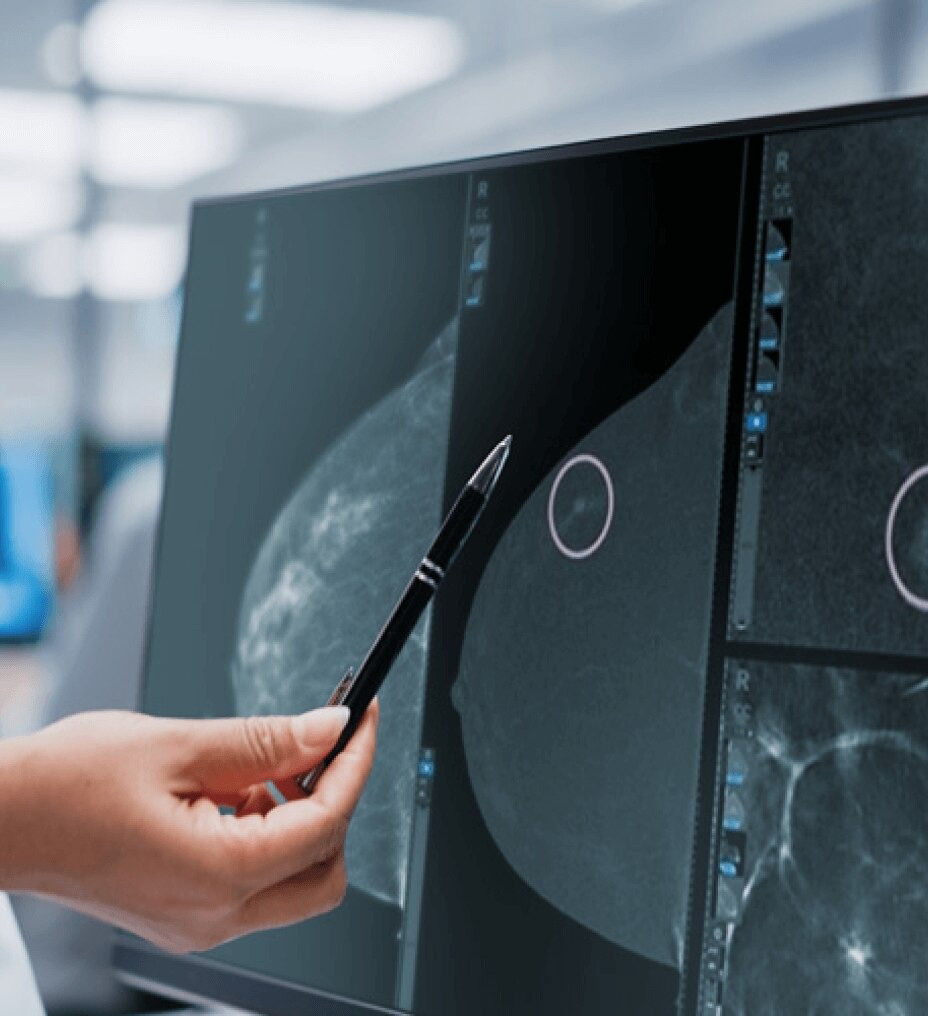

Fast procedure

CEM biopsy can be done within 15 minutes1.

Patient preferred

2 out of 3 patients prefer CEM to MRI2.

Lower cost

MRI diagnostic with biopsy is 51%3 more costly than CEM diagnostic & biopsy.

Efficient

Switch to interventional on the same system within your current room in 2 minutes4.